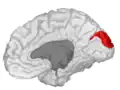

![]() Medial surface of left cerebral hemisphere. (Cuneus visible at left in red.) | |

Position of cuneus(red) of left cerebral hemisphere. -